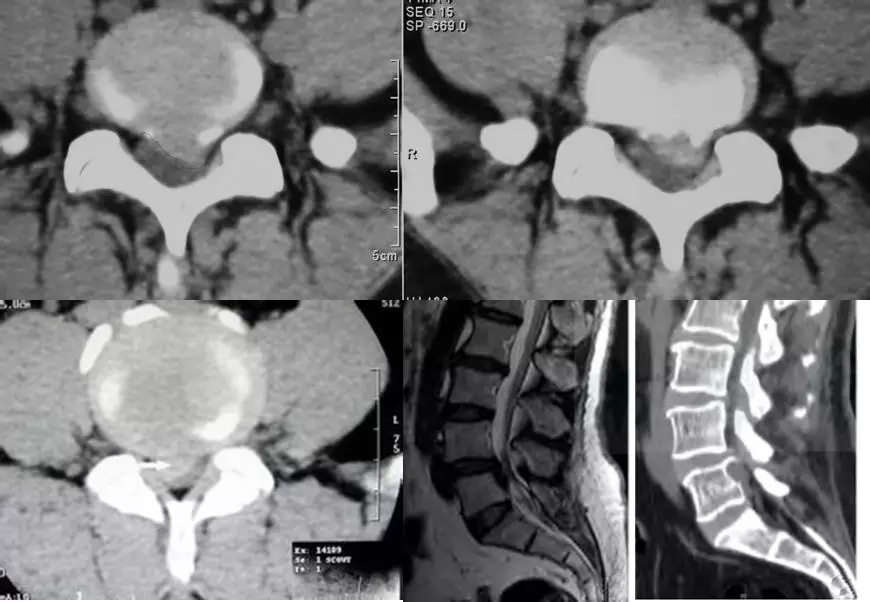

脊椎退行性变的CT表现

椎间盘向四周均匀膨出于椎体边缘,其后缘正中仍保持前凹的形态。

硬膜囊前缘及椎间孔可受压。

膨出的椎间盘外周可有弧形钙化,有时可显示椎间盘“真空”征和髓核钙化。

骨结构改变:多表现为椎体边缘部唇样骨增生、硬化。

黄韧带肥厚、钙化:表现为椎板内侧高密度影,硬膜囊侧后缘受压、移位。

后纵韧带肥厚钙化或骨化:表现为椎体后缘的圆形或椭圆形高密度影,边缘清楚。

4.滑脱、峡部裂

腰椎前滑脱I度

椎弓峡部裂